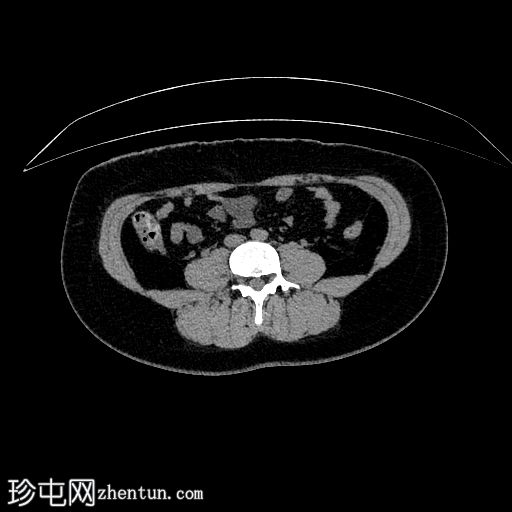

平扫CT

CT

左下腹可见卵圆形脂肪

性病

变,边缘密度增高,结肠周围脂肪组织呈条索状改变。

未见

泌尿

系统结石。